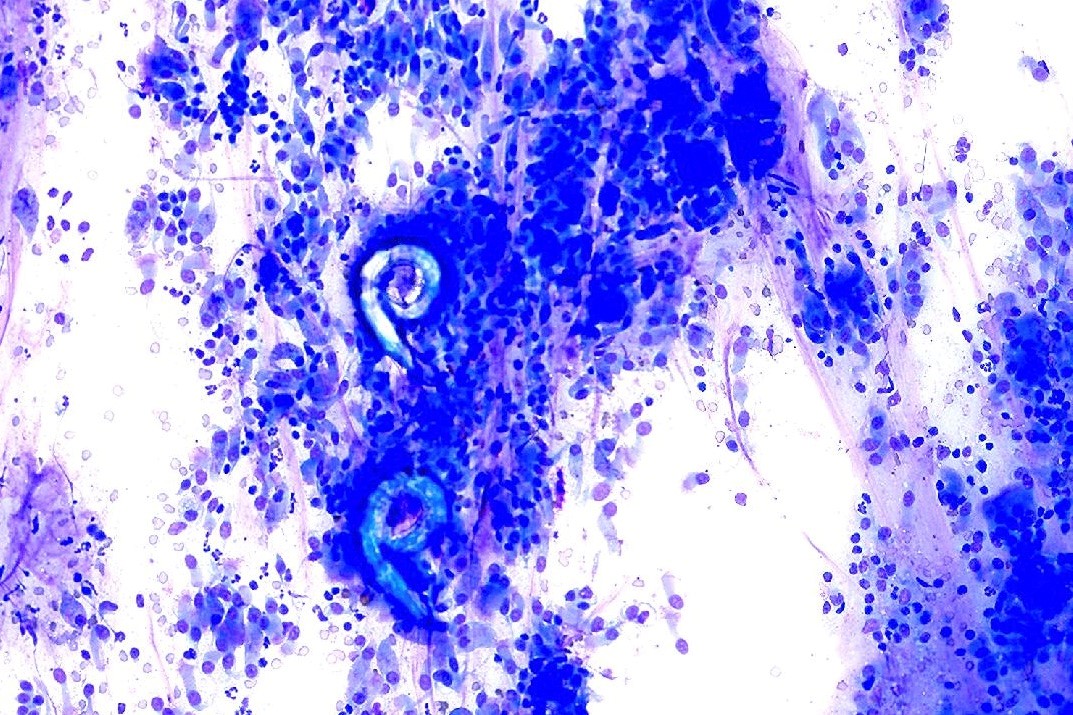

Kitten with intermittent cough

A transoral wash is obtained. A slide prepared for cytologic evaluation is shown: